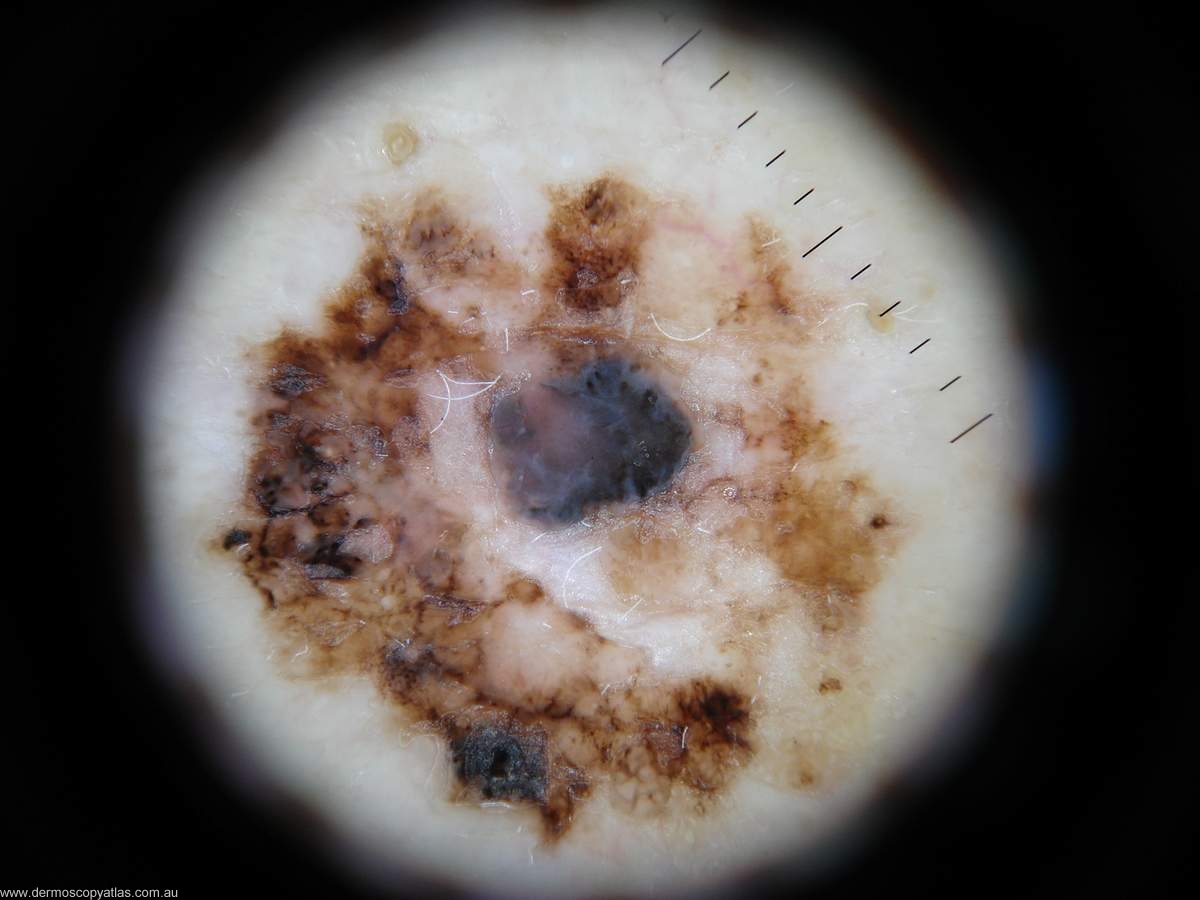

Question: How would you interprit this melanocytic lesion using the Menzies method?

Answer: Well the pigment pattern is asymmetrical and there are several colours. There is a blue white veil.radial streaming, scar like regression, brown dots. This is undoubtedly a malignant melanoma